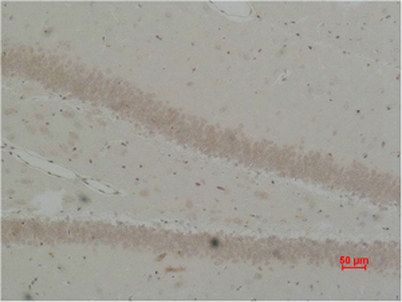

| Product name: | BEST2 rabbit pAb |

| Dilutions: | WB: 1:500-1000 IHC: 1:200-500 |

| Immunogen: | Synthetic Peptide of BEST2 |